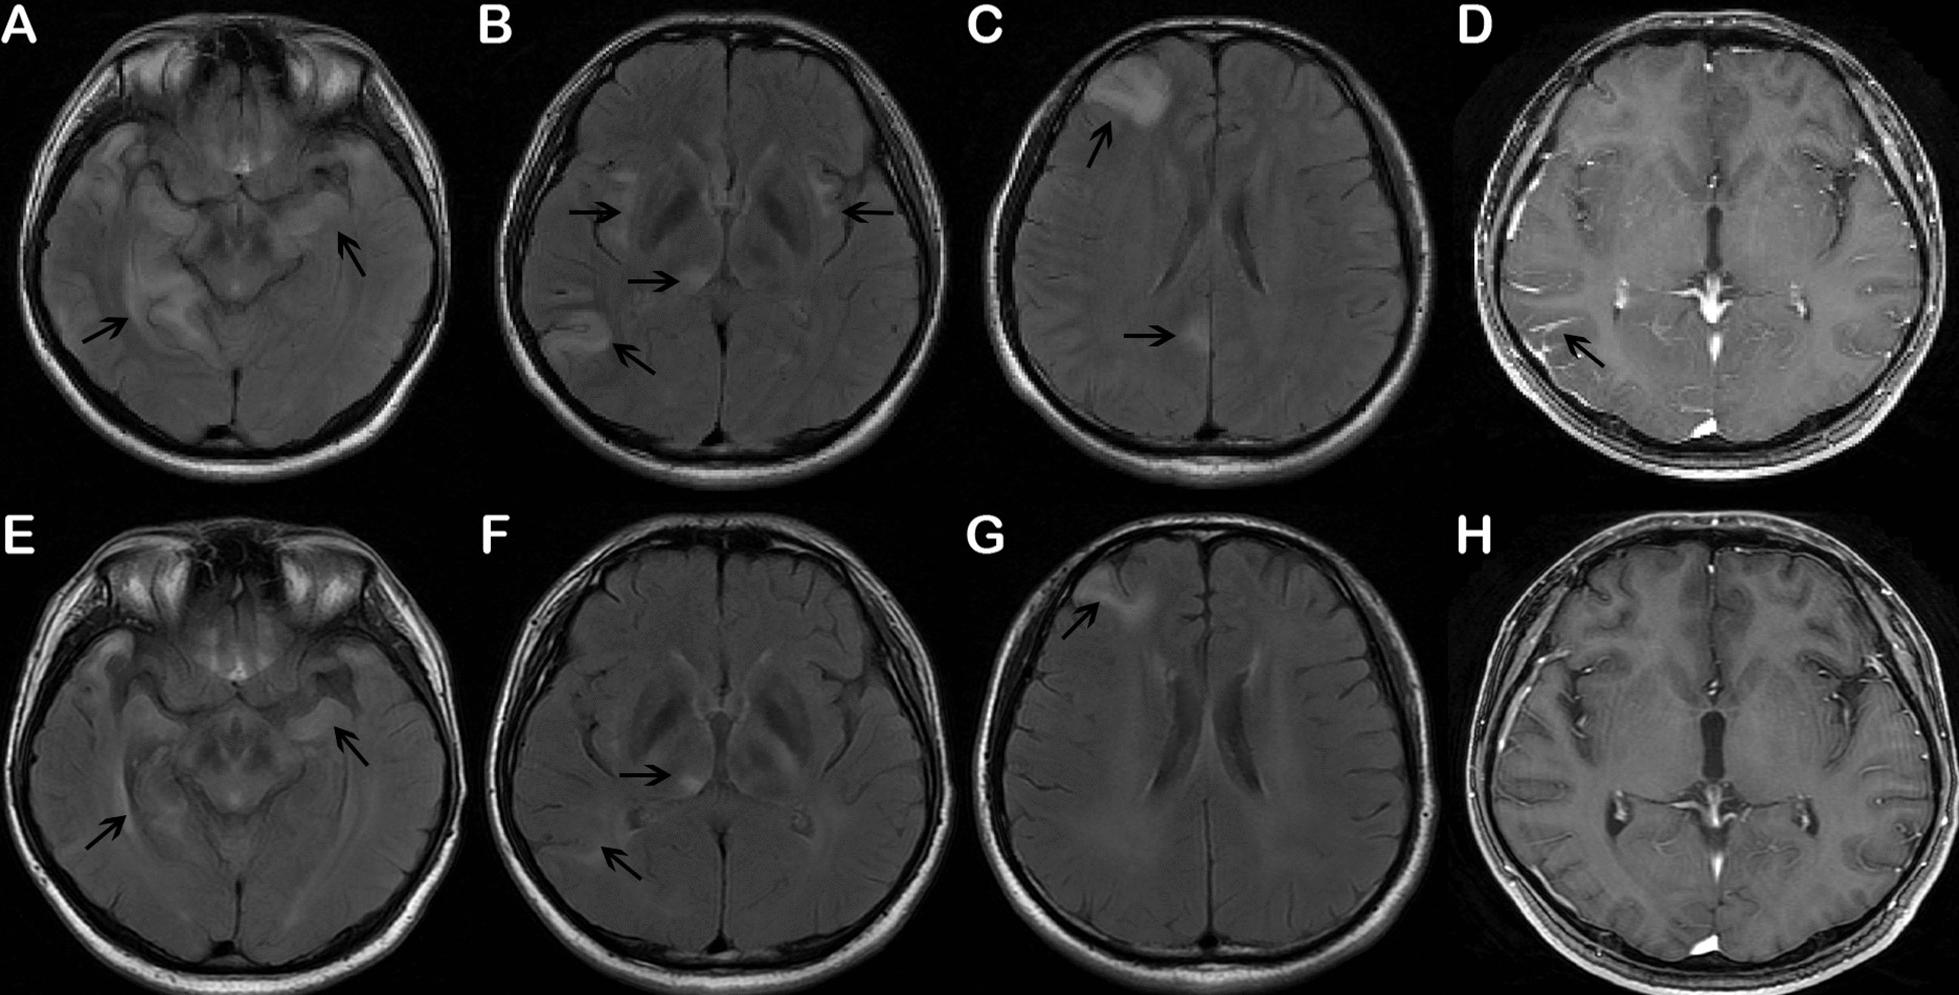

In this report, we describe a case of neurosyphilis in a HIV-negative, 29-year-old man, who was admitted to our hospital with an epileptic seizure and progressive cognitive impairment. Brain magnetic resonance imaging (MRI) revealed fluid-attenuated inversion recovery (FLAIR) high signal intensities in bilateral medial and anterior temporal lobes, insula, right pulvinar of the thalami, precuneus, frontal and temporo-occipital lobes. Laboratory examination showed positive results by means of nontreponemal or specific treponemal test in serum and CSF. mNGS of the CSF was also performed to identify Treponema pallidum for the first time.

本报告描述了一例 HIV 阴性的 29 岁男性神经梅毒病例,该患者因癫痫发作和进行性认知障碍而入院。脑磁共振成像(MRI)显示双侧内侧和前颞叶、岛叶、丘脑右侧豆状核、楔前叶、额叶和颞枕叶的液体衰减反转恢复(FLAIR)高信号强度。实验室检查显示血清和 CSF 中的非密螺旋体或特异性密螺旋体试验均呈阳性结果。CSF 的 mNGS 也是首次用于鉴定苍白密螺旋体。